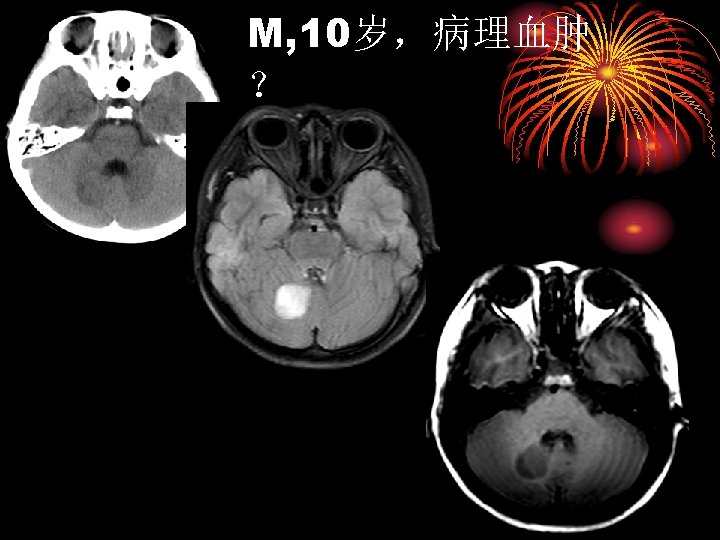

胶母 MR imaging and CT findings in 54 -year-old woman with glioblastoma. A, Axial T 2 -weighted and, B, contrast-enhanced axial T 1 -weighted MR images show a round cystic mass with complete rim enhancement and peritumoral edema in the subcortical white matter of the right frontal lobe. The signal intensity of the rim is isointense to gray matter on the T 2 -weighted image (arrow). C, Unenhanced axial CT image demonstrates isoattenuation (grade 2) of the rim (arrowhead).

胶母 Glioblastoma Multiforme: no dark line of advancing demyelination